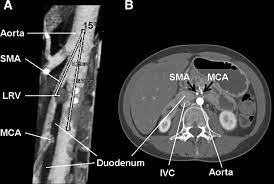

Superior Mesenteric Artery Syndrome Accompanying With Nutcracker Download Scientific Diagram

Axial Ct Section Demonstrating The Anatomy Of Sma Syndrome Download Scientific Diagram

Superior Mesenteric Artery Syndrome Coexists With Nutcracker Syndrome In A Female A Case Report Bmc Gastroenterology Full Text